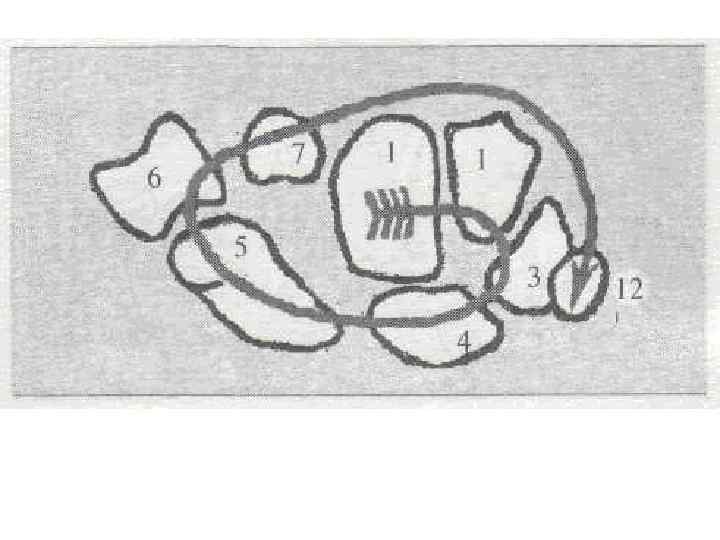

ЛУЧЕЗАПЯСТНЫЙ СУСТАВ И КИСТЬ - т. о. в дист. эпифизе луч. кости - 1 -2 года - т. о. в дист. эпифизе локт. кости - 7 -8 лет - синост-ие - 17 -21 год женщины, 19 -23 года мужчины. Кости запястья - - головчатая и крючковидная - 9 мес внутриутробно - 3 мес - трехгранная - 3 года - полулунная - 4 года - ладьевидная - 5 лет - трапециевидная и трапеция - 6 -7 лет - гороховидная - 8 -12 лет у девочек, 10 -15 лет у мальчиков. Кости пясти и фаланги пальцев (моноэпифизарные кости) - т. о в истинном эпифизе ( у 1 -ой пястной кости - проксимальный, у всех костей - дистальный ) - 1 -2, 5 года - синост-ие 1 -ой пястной кости -14 лет - синост-ие остальных костей – 19 -23 года мужчины, 17 -21 год женщины

ЛУЧЕЗАПЯСТНЫЙ СУСТАВ И КИСТЬ - т. о. в дист. эпифизе луч. кости - 1 -2 года - т. о. в дист. эпифизе локт. кости - 7 -8 лет - синост-ие - 17 -21 год женщины, 19 -23 года мужчины. Кости запястья - - головчатая и крючковидная - 9 мес внутриутробно - 3 мес - трехгранная - 3 года - полулунная - 4 года - ладьевидная - 5 лет - трапециевидная и трапеция - 6 -7 лет - гороховидная - 8 -12 лет у девочек, 10 -15 лет у мальчиков. Кости пясти и фаланги пальцев (моноэпифизарные кости) - т. о в истинном эпифизе ( у 1 -ой пястной кости - проксимальный, у всех костей - дистальный ) - 1 -2, 5 года - синост-ие 1 -ой пястной кости -14 лет - синост-ие остальных костей – 19 -23 года мужчины, 17 -21 год женщины